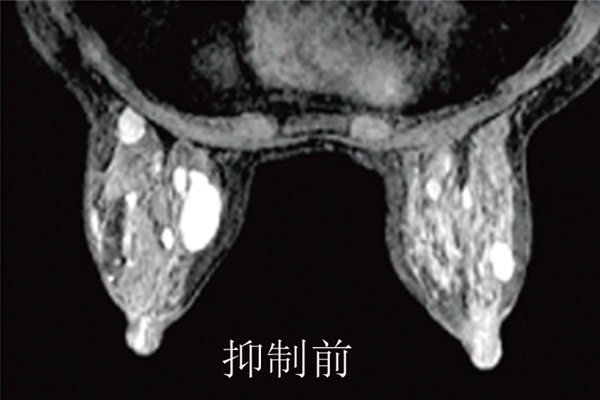

奧洛瑞專利的RODEO脈沖序列,具有充分的脂肪影像抑制和乳腺管影像抑制,能有效地減少影像的偽影,尤其是心臟跳動(dòng)與呼吸所產(chǎn)生的移動(dòng)偽影,因此能產(chǎn)生更加清晰的影像,提高病灶的檢測(cè)能力。